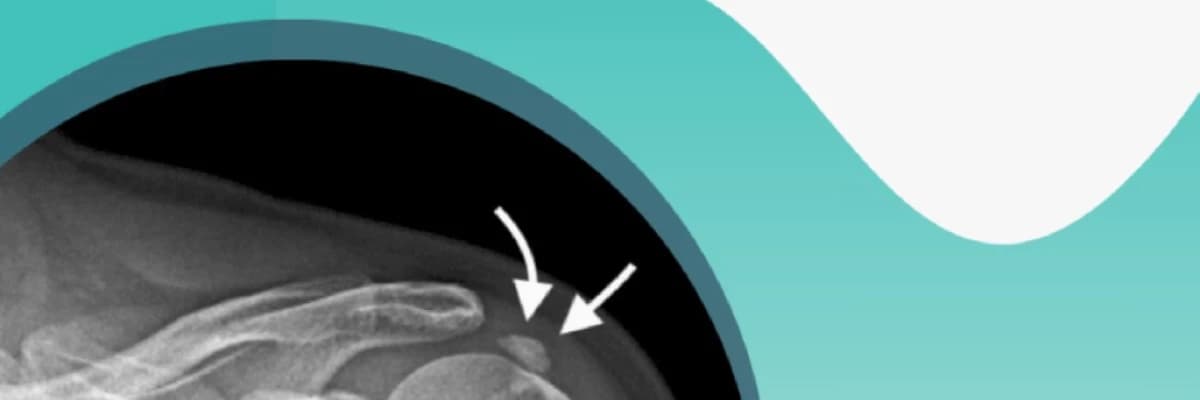

Kalsifik tendinit, genellikle omuzda meydana gelen bir tür tendinittir. Bu durumda, tendonlarda kalsiyum birikintileri oluşur ve ağrıya, sertliğe ve omuzda fonksiyon kaybına neden olabilir. Kalsifik tendinitin nedeni tam olarak bilinmemektedir, ancak tekrarlayan stresli hareketlerin, yaralanmaların ve hormonal faktörlerin rol oynadığı düşünülmektedir.